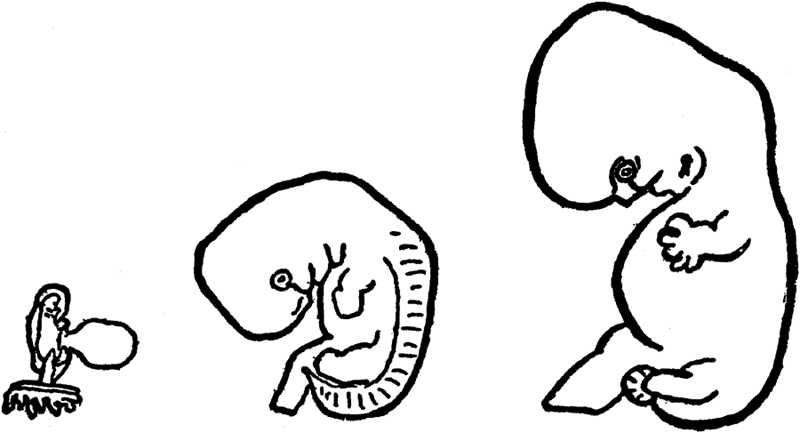

| X. | Pregnancy | 88 |

Period of Pregnancy in Human Female—Physiologic Process of Pregnancy—Growth of Embryo from Moment of Conception—Pregnant Woman Provides Nourishment for Two—Her Excreting Organs Must Work for Two. |

| XIII. | The Size of the Fetus | 105 |

Approximately Correct Measurements and Weight of Fetus at End of Each Month of Pregnancy. |